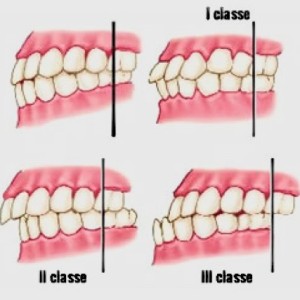

- Correggerie una Classe Molare scorretta: Si distinguono 3 classi di maleocclusioni in base alla relazione dei primi molari.

- Prima classe: relazione dei molari normali

- Seconda classe: molare inferiore posizionato “dietro” rispetto al molare superiore.

- Terza classe: molare inferiore posizionato “davanti” al molare superiore.

La classe molare è come l’ingranaggio corretto che permette alla dentatura posteriore di “funzionare” in modo corretto, così da poter triturare agevolmente il cibo senza difficoltà.